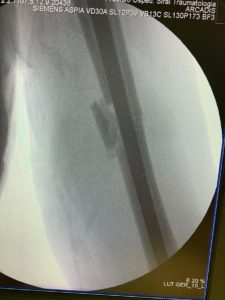

A questo punto, parole di Xaver Mir: «Si poteva ricostruire la continuità dell’osso inserendo nel suo canale interno un chiodo endomidollare di titanio», oppure si poteva applicare una placca in titanio da avvitare su un lato dei monconi. Il dottor Xavier Mir ha optato per la seconda scelta: ha praticato un’ampia incisione sul versante postero-laterale del braccio; ha isolato il nervo radiale; poi ha fissato con 10 viti una lunga placca di titanio direttamente alla parte esterna dell’omero fratturato, raddrizzandolo. Quindi ha fissato un frammento osseo, che si era staccato, con due viti ai monconi maggiori. In tutto 12 viti. Con questa tecnica si vuole che la placca funga da “stampella” all’omero e, su questa guida si formi il callo fibroso, e poi osseo. Si paga, tuttavia, il prezzo di un ampio taglio e 12 viti che, perforando l’osso, lo indeboliscono intaccandone la continuità strutturale.

E’ stata una buona scelta? Secondo la “AO Trauma Foundation” lo è stata. Secondo il mitico Claudio Costa, no. Lui l’aveva detto subito: «…per accelerare i tempi di recupero bisognava intervenire con un chiodo endomidollare, non con una placca. […] Avrei consigliato di rischiare un po’ e di mettere un chiodo, per fare un impianto più affidabile dal punto di vista della traumatologia motociclistica. Probabilmente, hanno pensato che con una placca più grande e più viti, l’impianto potesse tenere; me lo auguro. Il chiodo, probabilmente, viene tenuto come emergenza in caso di malaugurata sfortuna».

E la “sfortuna” c’è stata. Dopo 3 giorni dall’intervento Marc Marquez è salito in moto, per fare un giro di prova, e la placca si è rotta. Alla fine del giro, il campione non sentiva più la mano. Brutto segno di compromissione dei nervi del braccio. Adesso il braccio è inutilizzabile.

Dalla radiografia si vede chiaramente che la placca, con le sue 12 viti, non può dare la certezza dalla guarigione senza altre rotture in caso di banali cadute. E si vede chiaramente che, invece, il chiodo endomidollare, mostrato nella radiografia di un altro paziente fratturato di omero, operato a Carbonia, dà più sicurezza. Se il povero Marc Marquez si fosse fratturato l’omero nei tornanti del Sulcis Iglesiente sarebbe stato operato da noi con l’inserimento di un solido “chiodo endomidollare”, ma ad una condizione: avrebbe dovuto aspettare in “lista d’attesa” per 8-10 giorni, come tutti, perché da un po’ di tempo i nostri Ospedali sono carenti di Anestesisti ed Ortopedici. E bisogna aspettare. Ma Marc Marquez non aspetta.